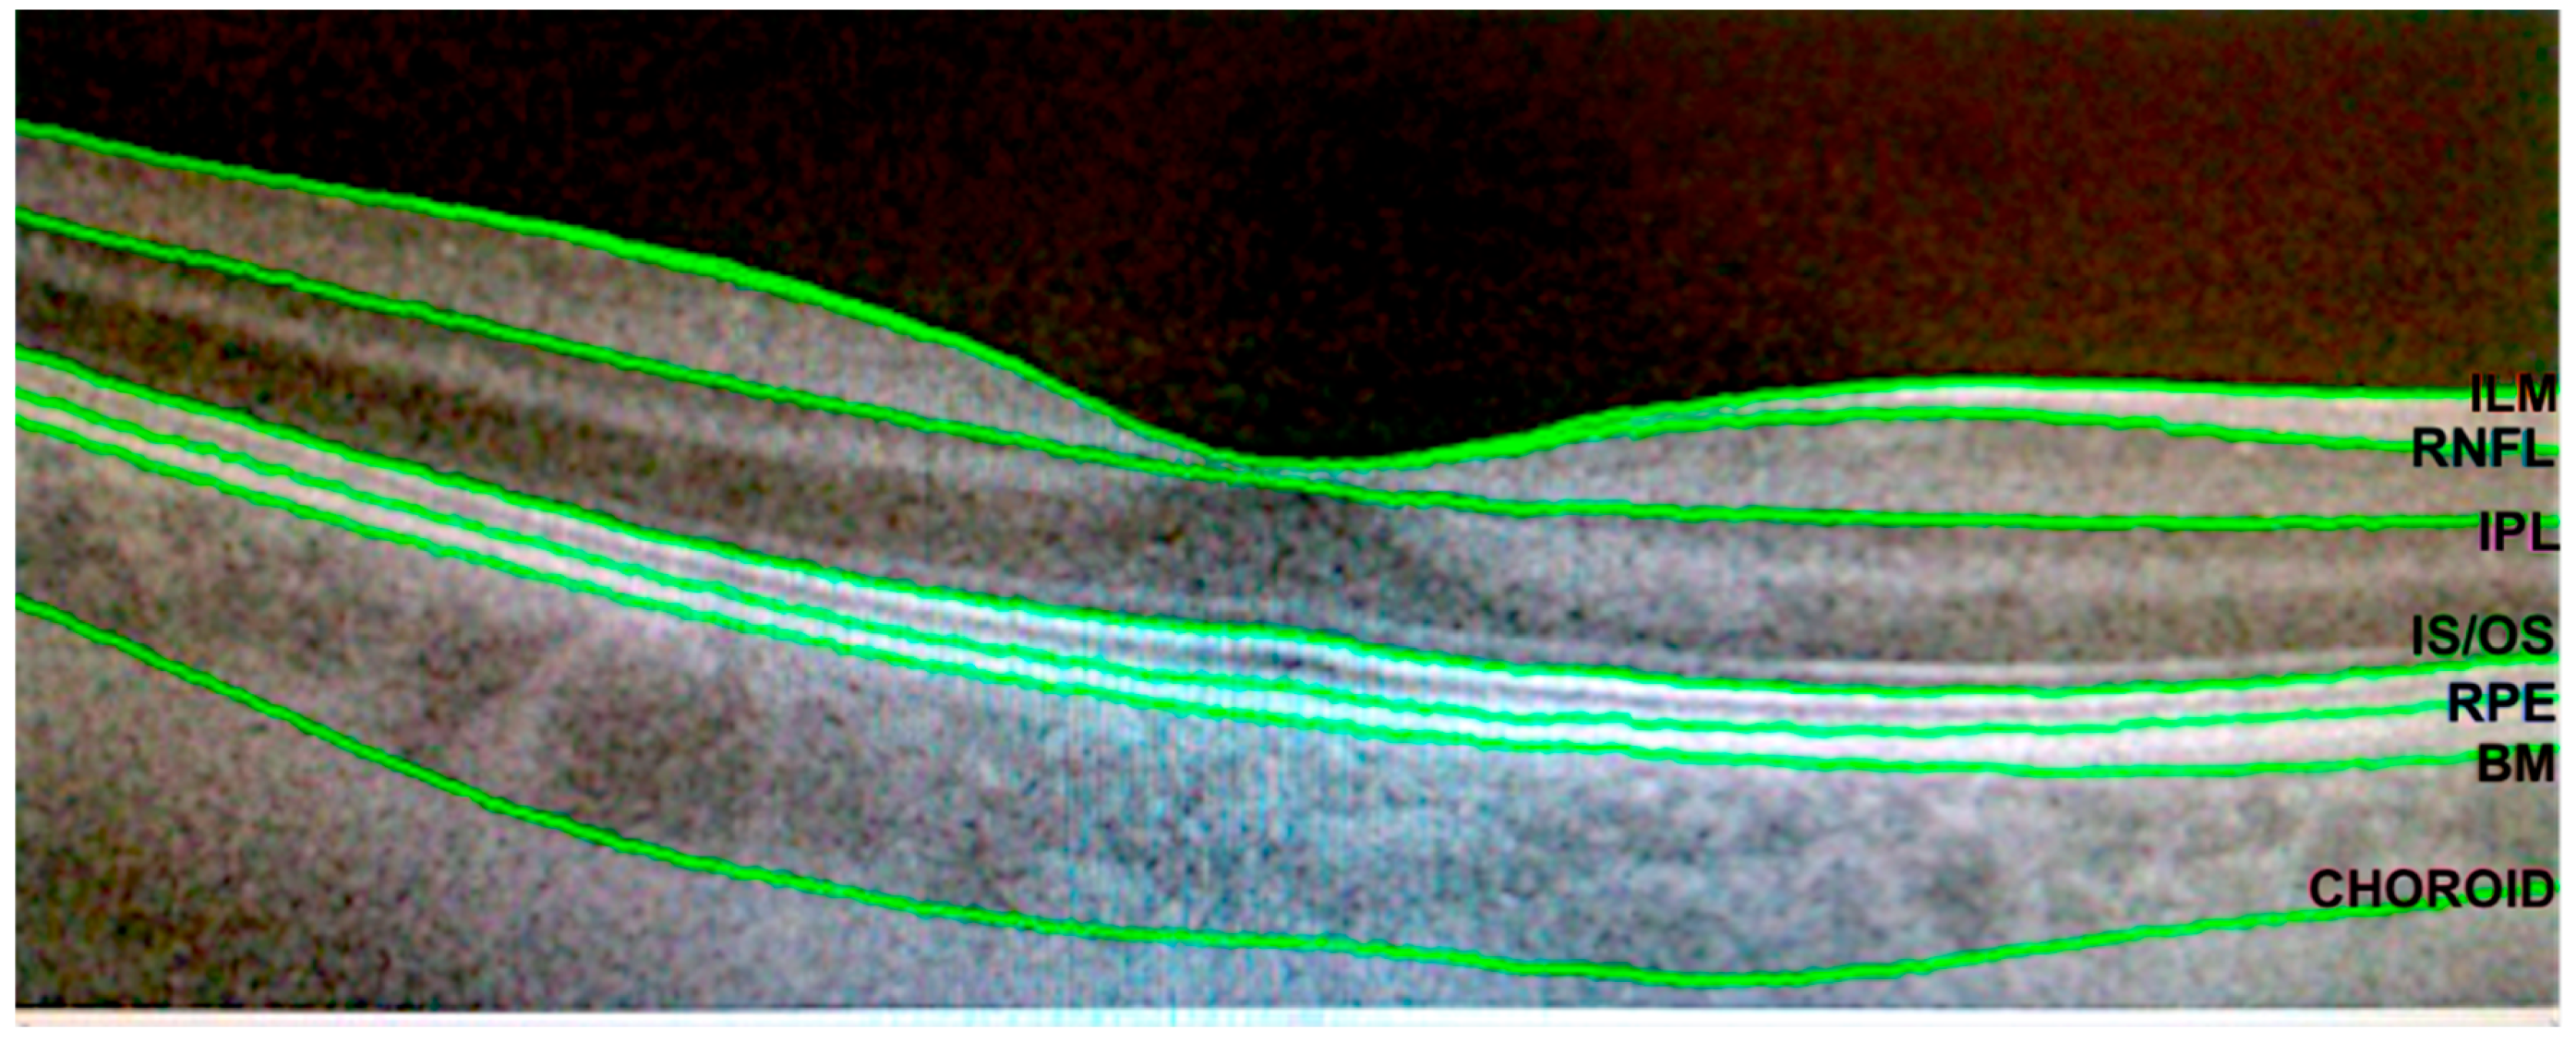

- Pérez Del Palomar, A.; Cegoñino, J.; Montolío, A.; Orduna, E.; Vilades, E.; Sebastián, B.; Pablo, L.E.; Garcia-Martin, E. Swept source optical coherence tomography to early detect multiple sclerosis disease. The use of machine learning techniques. PLoS ONE 2019, 14, e0216410. [Google Scholar] [CrossRef] [PubMed]